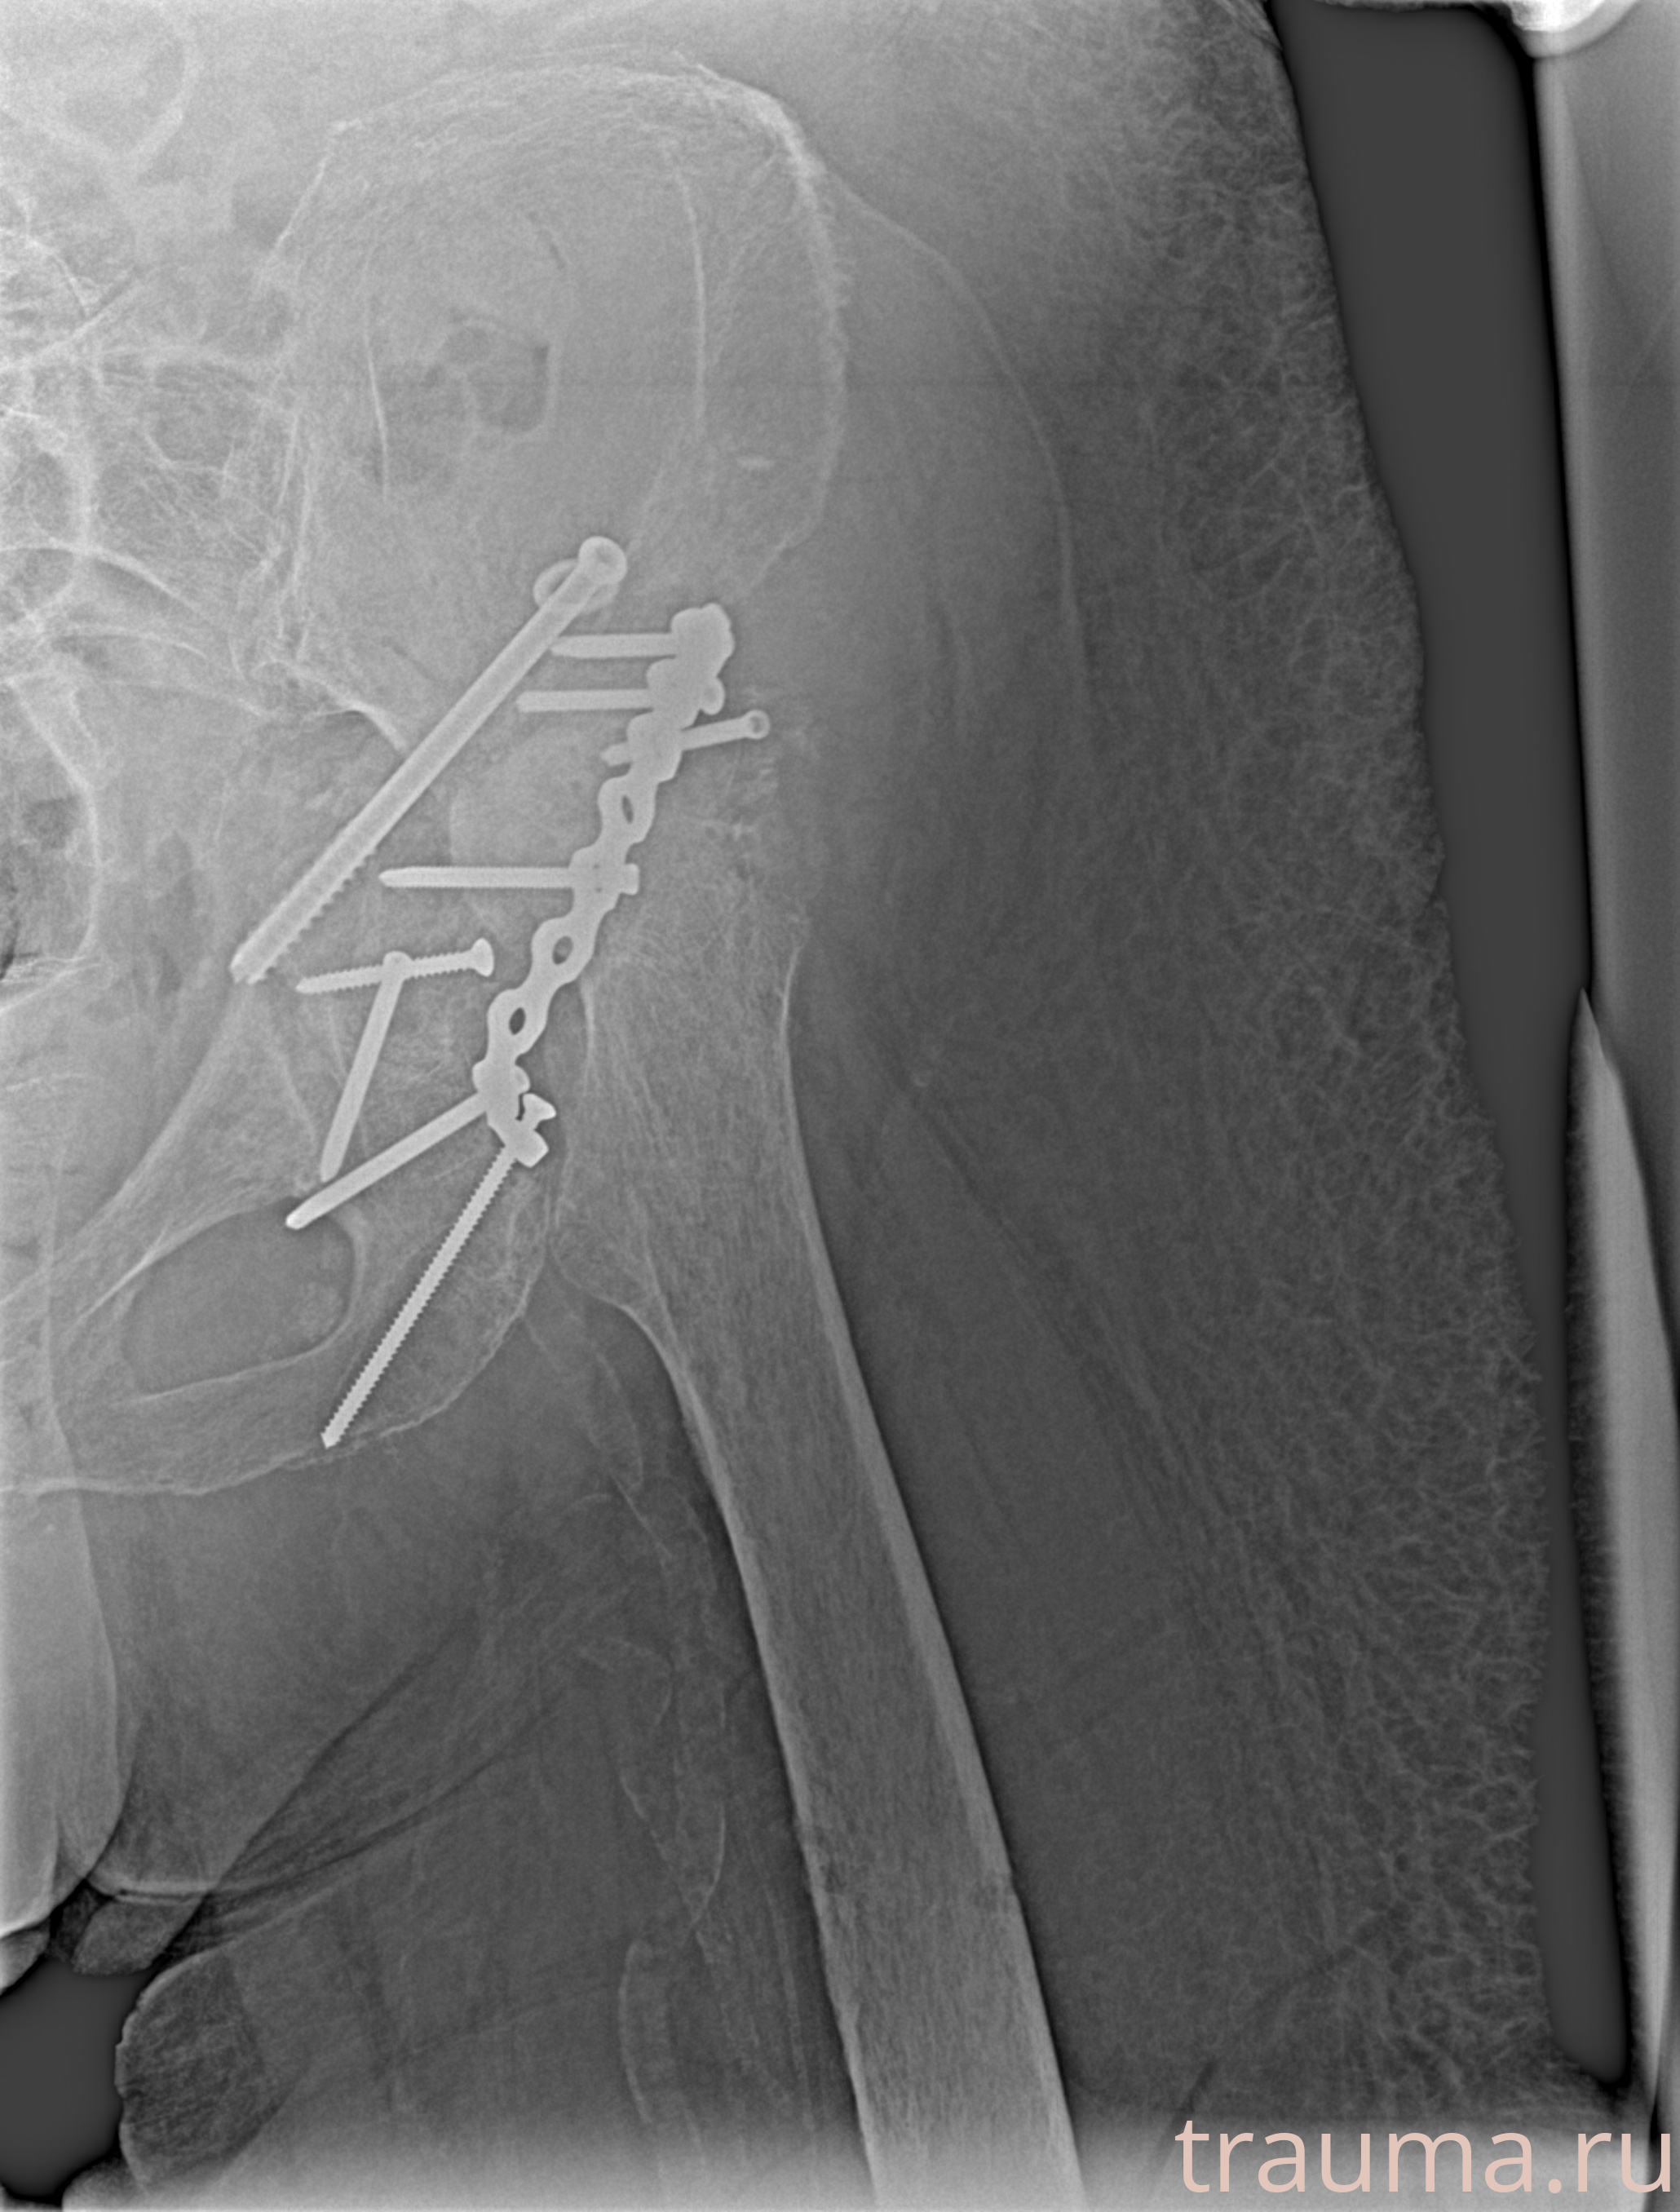

Рентгенограммы